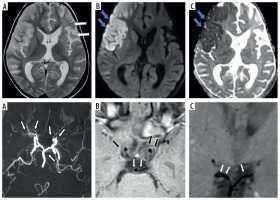

Figure 4

Two-year-old female presenting with left hemiparesis and seizures. Axial T2 (A), axial diffusion-weighted imaging (DWI) (B) and axial apparent diffusion coefficient (ADC) map (C) images show volume loss with encephalomalacic changes in left fronto-parietal region (white arrows in A) along with acute infarct involving right fronto-parietal lobe with diffusion restriction (blue arrows in B and C). Axial maximum intensity projection time-of-flight magnetic resonance angiography (MRA) image (D) shows stenotic bilateral supraclinoid internal carotid artery (ICA), right terminus ICA, occluded left terminus ICA, B/L anterior cerebral artery (ACA), B/L middle cerebral artery (MCA) with normal B/L posterior cerebral artery (PCA) and distal basilar artery (BA) (white arrows in D). Axial (E) and coronal post-contrast vessel wall imaging (VWI) (F) showing vessel wall thickening and grade 1 concentric enhancement of B/L supraclinoid ICAs (black arrows in E) with grade 1 concentric enhancement in bilateral PCA and distal BA (small white arrows in E and F)